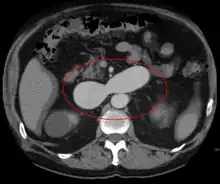

An arterial venous malformation of the left kidney and a simple cyst of the right kidney